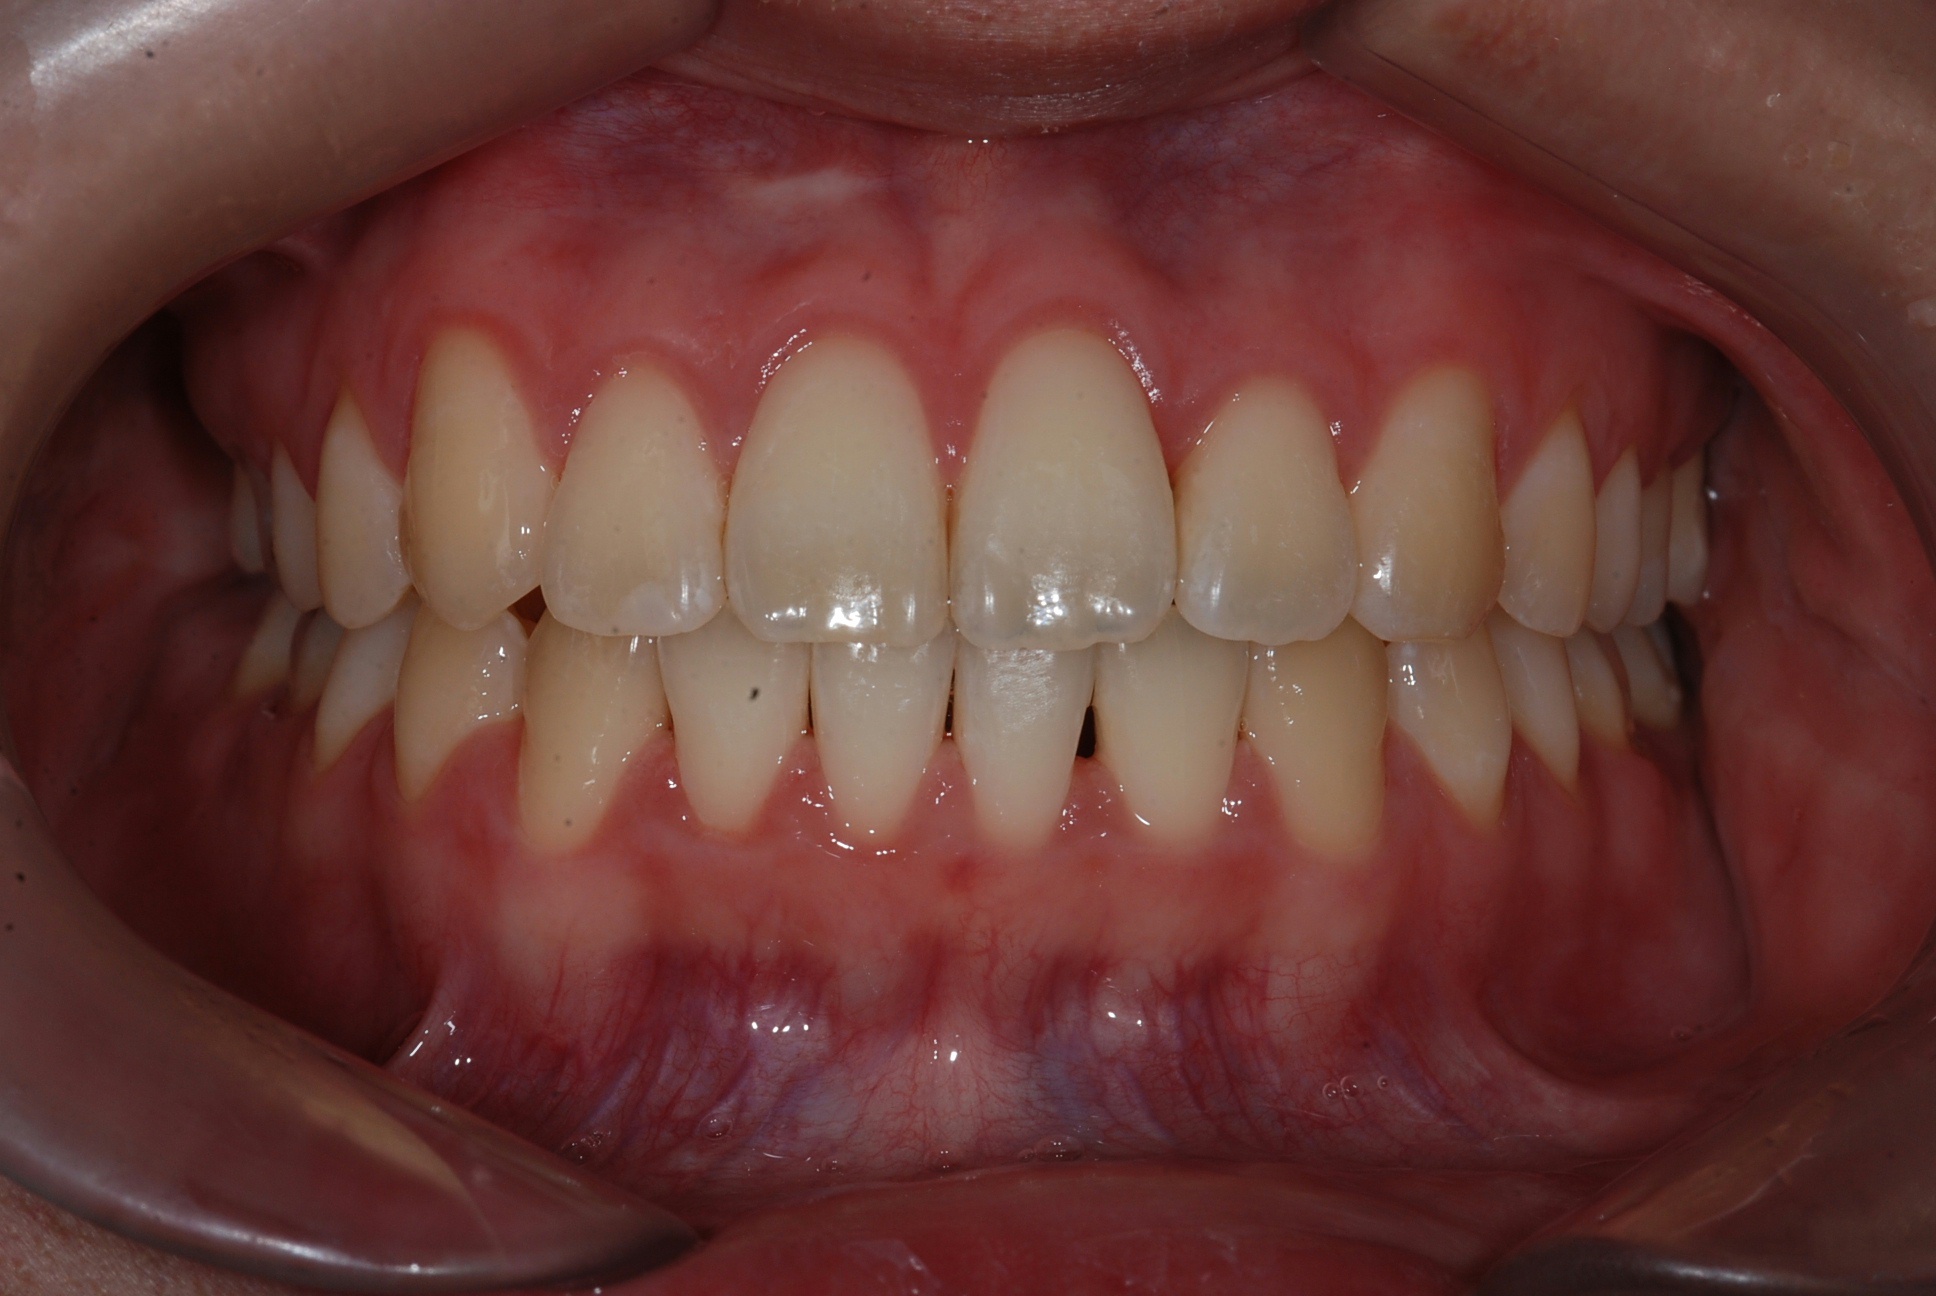

치료 후 사진입니다.